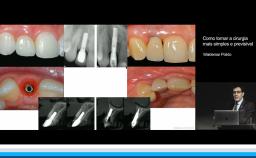

Surgical Planning and Procedures

Esta conferência discute a cirurgia guiada assistida por computador, em maxila totalmente edêntula. As guias cirúrgicas são desenhadas e impressas a partir do planejamento cirúrgico em ambiente virtual, com a utilização de programas de software de planejamento que associam exames de tomografia computadorizada (CT) da anatomia óssea do paciente ao planejamento protético. Apresenta evidências científicas sobre a vantagens clinícas e acuracidade na transferência do posicionamento do implante guiado em comparação com a instalação de implantes a mão livre. Concluindo que, por meio da sistematização do planejamento, junto a procedimentos cirúrgicos guiados, é possível otimizar a cirurgia, minimizar complicações e oferecer mais conforto para o paciente.